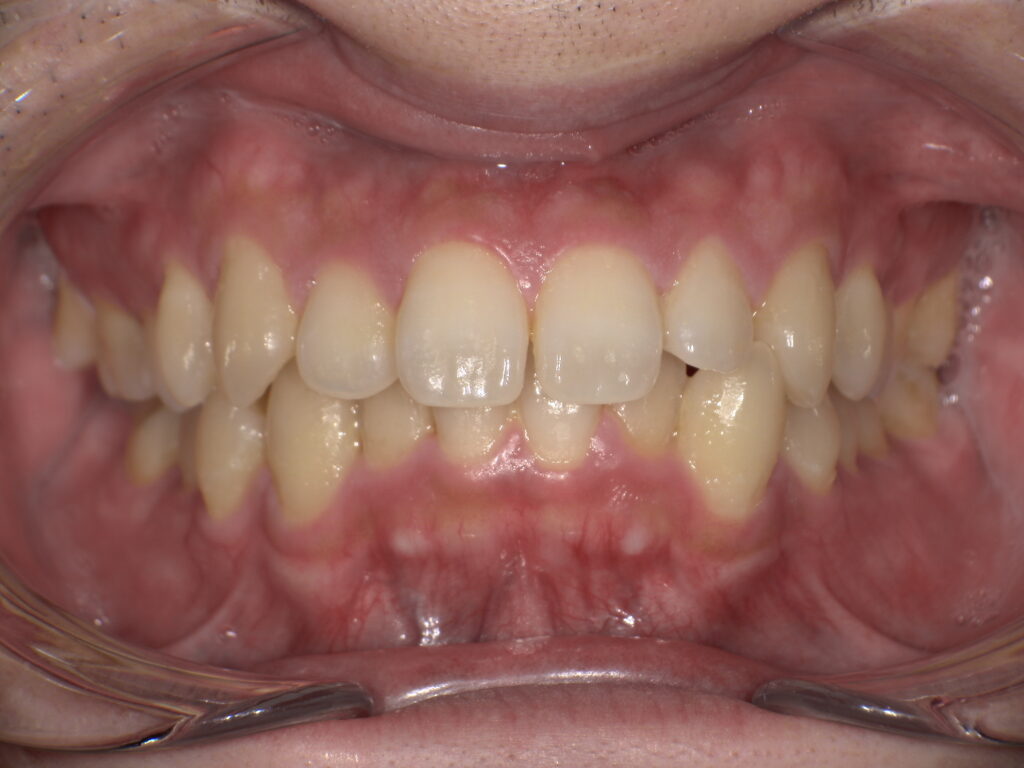

・染め出しとホームケアの確認

P①で最も重要なステップの一つです。歯周病治療の成功は、患者さんのご自宅での**ブラッシング(セルフケア)**にかかっていると言っても過言ではありません。染め出し液を使用し、磨き残しの部位を特定。患者さんの癖や歯並びに合わせた、効果的な歯ブラシの動かし方や、フロス・歯間ブラシの正しい使い方をマンツーマンで確認します。

↑きれいに見えていても、↓染め出しをするとこんなにも磨き残しがたくさんあります。

※患者様の許可を得て記載しております。